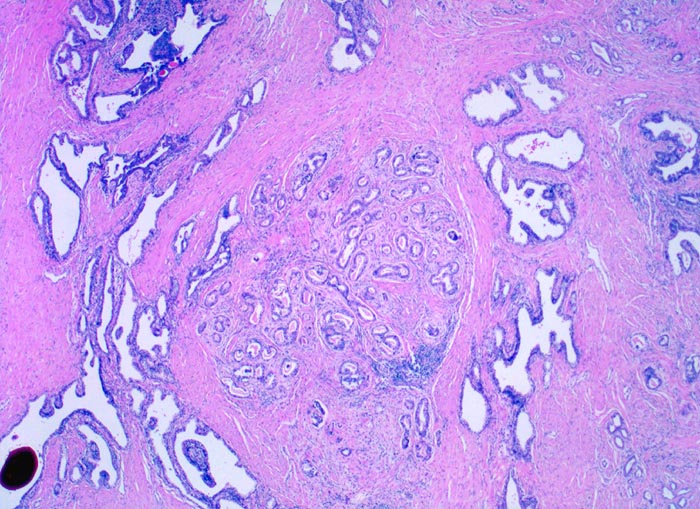

Neben grossen normalen Prostatadrüsen mit grossen Lumina ist in der Übersicht ein gut umschriebener Herd dicht gelagerter mittelgrosser gut geformter Drüsen mit intraluminalem Sekret erkennbar. Innerhalb dieses Karzinomherdes sind keine normalen Drüsen erkennbar. Das Karzinom infiltriert also nicht das Normalgewebe. Dieser Tumorherd entspricht einem Gleason Grad 2.

Eingedicktes Sekret mit Ausbildung eines Corpus amylaceum in einer benignen Drüse.

Die Diagnose eines Prostatakarzinoms lässt sich bereits in der Übersichtsvergrösserung aufgrund der Ansammlung kleiner Drüsen stellen. Ein umschriebenes noduläres Infiltrat grösserer gut geformter Karzinomdrüsen, welches das normale Prostatagewebe intakt lässt, entspricht einem Gleason Grad 2.

Der histologische Grad eines Prostatakarzinoms korreliert mit dem Progressionsrisiko. Das Grading nach Gleason umfasst einen Wert zwischen 1 (gut differenziert) und 5 (wenig differenziert) und berücksichtigt die Architektur der Karzinomdrüsen. Prostatakarzinome sind oft heterogen bezüglich Differenzierung. Der Gleason Score wird ausgedrückt als Summe der beiden prädominanten Wachstumsmuster. Das häufigere Muster wird dabei zuerst genannt. Ein Gleason Score: 4+3=7 bedeutet, dass das Wachstumsmuster entsprechend einem Gleason Grad 4 dominiert. Bei einem Tumor, der zu mehr als 95% ein einheitliches Wachstumsmuster zeigt wird der entsprechende Gleason Grad zweimal gezählt. Bsp. 3+3=6.

Tumoren mit einem Gleason Score bis 6 sind hoch differenziert, mit einem Gleason Score 7 bis 8 mässig und einem Gleason Score 9 bis 10 schlecht differenziert.